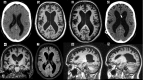

Behavioural variant frontotemporal dementia (bvFTD) and idiopathic normal pressure hydrocephalus (iNPH) are neurodegenerative diseases that can present with similar symptoms. These include decline in executive functions, psychomotor slowness, and behavioural and personality changes. Ventricular enlargement is a key radiological finding in iNPH that may also be present in bvFTD caused by the C9ORF72 expansion mutation. Due to this, bvFTD has been hypothesized as a potential comorbidity to iNPH but bvFTD patients have never been identified in studies focusing in clinical comorbidities with iNPH. Here we describe a patient with the C9ORF72 expansion-associated bvFTD who also showed enlarged ventricles on brain imaging. The main clinical symptoms were severe gait disturbances and psychiatric problems with mild cognitive decline. Cerebrospinal fluid removal increased the patient's walking speed, so a ventriculoperitoneal shunt was placed. After insertion of the shunt, there was a significant improvement in walking speed as well as mild improvement in cognitive function but not in neuropsychiatric symptoms relating to bvFTD. Comorbid iNPH should be considered in bvFTD patients who have enlarged ventricles and severely impaired gait.